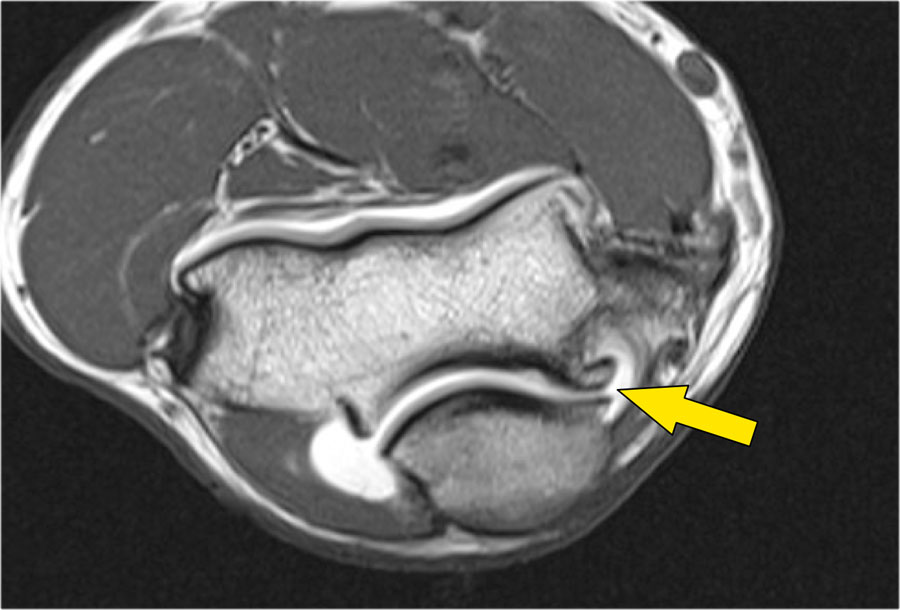

Khi quan sát trên lát cắt ngang (axial), chúng ta có thể nhận thấy sự hình thành gai xương khổng lồ.

Lưu ý rằng dây thần kinh trụ (mũi tên màu xanh) nằm cạnh các gai xương này và những bệnh nhân này có thể biểu hiện bệnh lý thần kinh trụ.